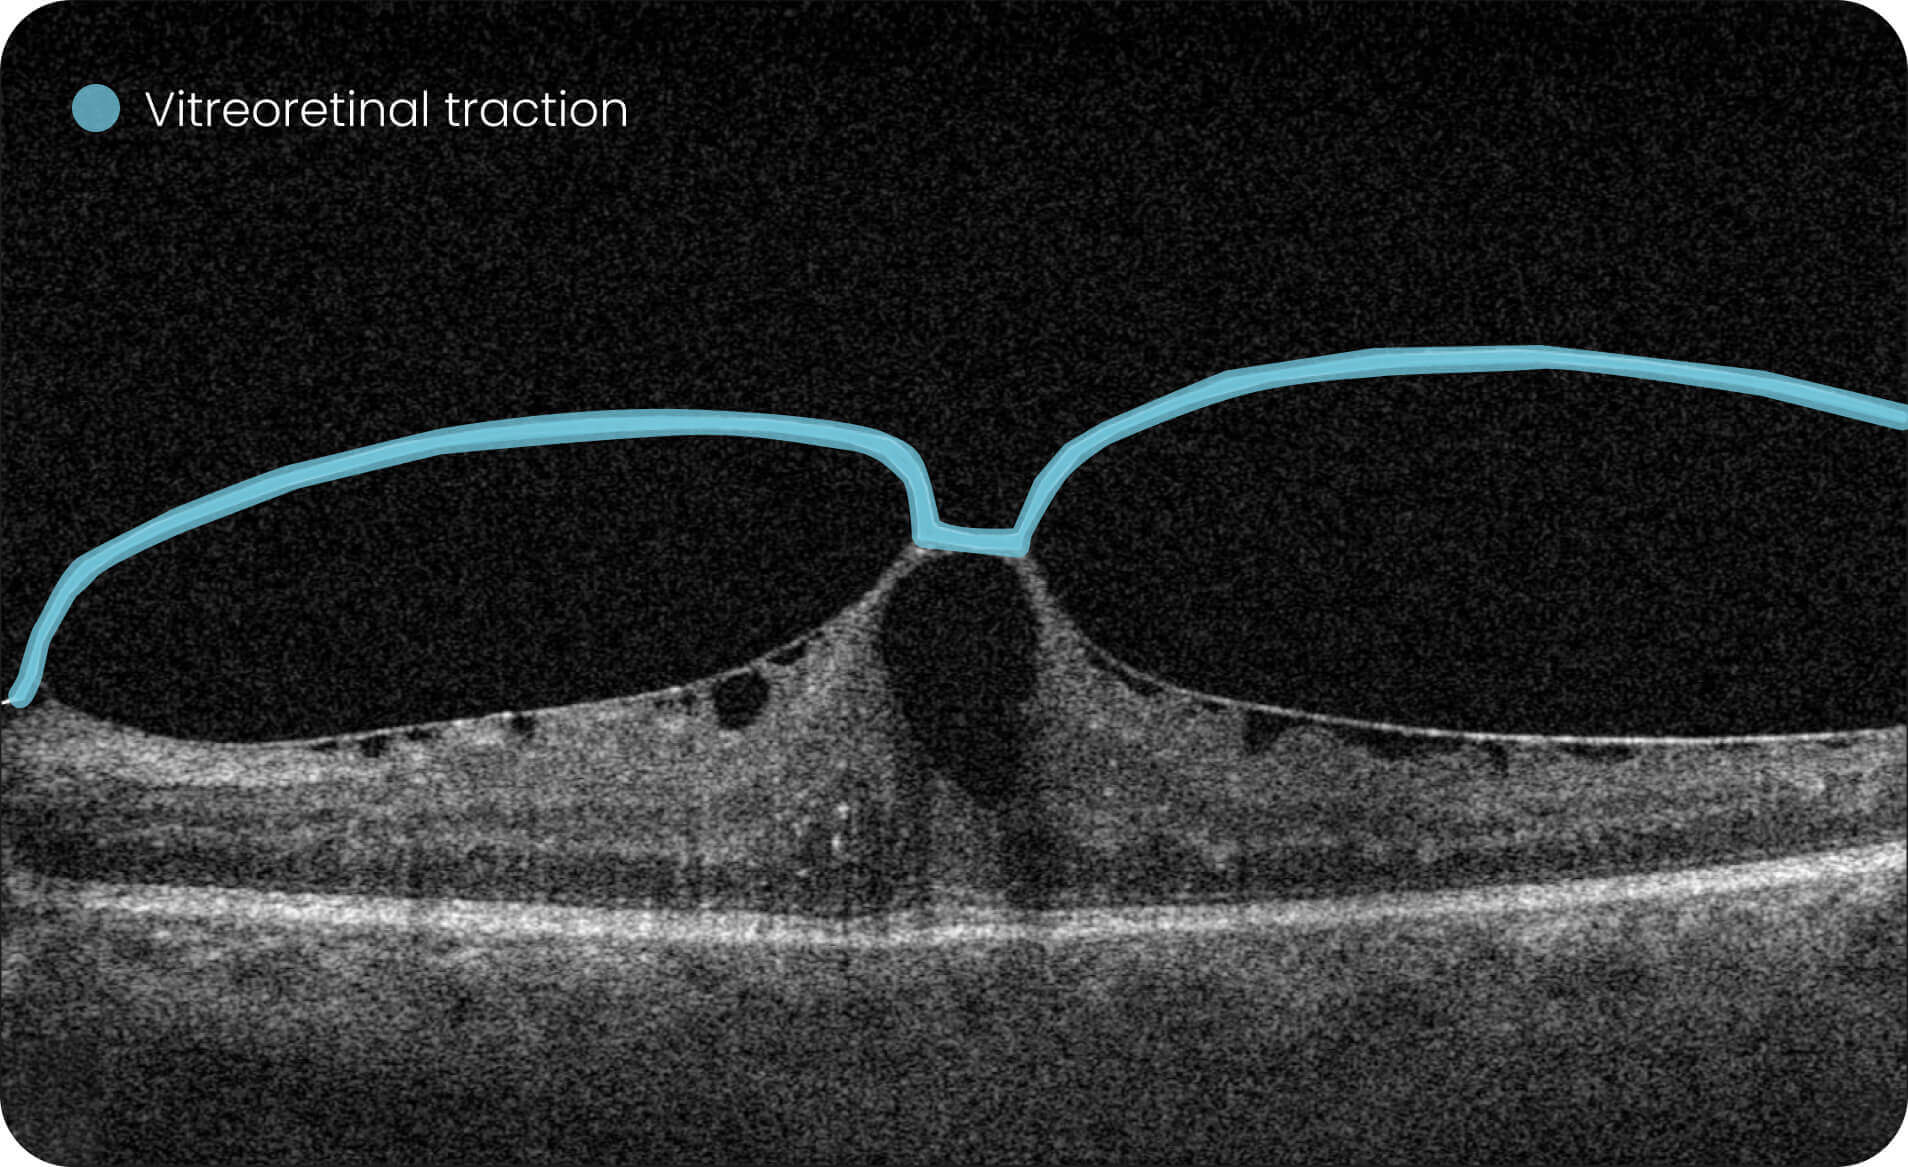

Characterization and visualization of OCT features commonly studied in Geographic Atrophy (GA), including hypertransmission, RPE atrophy, neurosensory retinal atrophy, and EZ changes.

The GA Progression feature provides tools for research-oriented visualization and comparison of OCT imaging data across multiple visits. Users can review changes in areas associated with geographic atrophy (GA) and related imaging features through percentage-based displays, maps, and graphs.

Quantitative, image-derived measurements of GA-related features and associated biomarkers for research analyses.

Altris is a web platform developed by professionals with expertise in retinal imaging. We’ve collected a large number of OCT scans, and our team has manually annotated thousands of them to develop the Altris system, an artificial intelligence geographic atrophy research USA platform, which can: